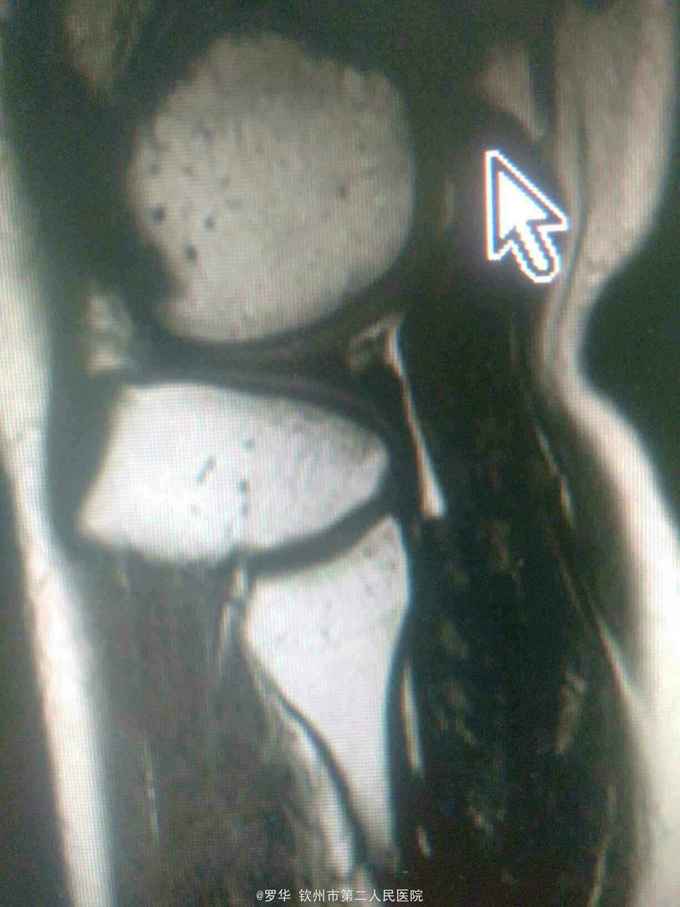

主诉:扭伤致左膝关节活动受限3月余。病史:患者男性,31岁,于入院3月余前扭伤左膝关节,致左膝关节肿痛、活动受限,尚可站立行走,但不能剧烈运动及重体力劳动,曾行磁共振检查提示左膝前交叉韧带损伤,半月板损伤,现为进上一步治疗入院。

查体:左膝关节无明显压痛,前抽屉试验阳性,侧方应力试验、麦氏征、研磨试验均阴性,膝关节屈伸活动可,余查体未见特殊。 辅查:膝关节磁共振提示左前交叉韧带损伤,左膝关节半月板损伤。

诊断:左膝关节前交叉韧带断裂,左膝关节半月板损伤。 治疗:予硬外麻下行左膝关节前交叉韧带重建术。